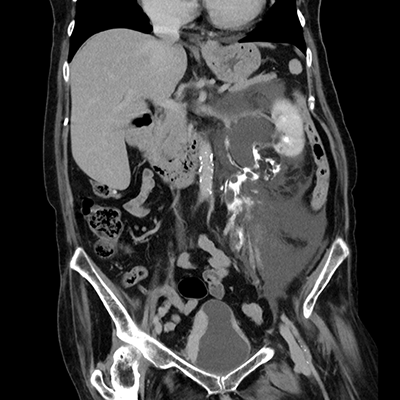

臨床画像例

中山氏 IPVは被ばく低減に役立っています。

当院では、体幹部は平均的にガイドライン*2比で50%近く低被ばくの条件で撮影していますが、読影の先生にも問題なく診断して頂いています。低被ばくに撮影することは、患者さんのメリットに繋がります。当院では、さらに患者さんに安心していただくため、被ばく線量を集計して患者さん向けの説明ツールを作っています。